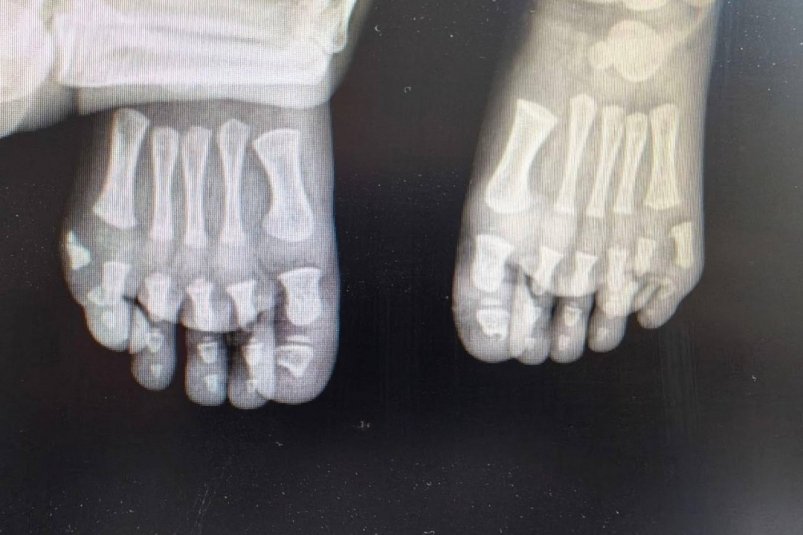

Лишние пальцы мешали ходить мальчику из Подмосковья

Рентгенография пресс-службы Минздрава Московской области

Фото: пресс-службы Минздрава Московской области

StolicaMedia, 14 апреля. В Подмосковье хирурги прооперировали мальчика с лишними пальцами на обеих стопах. Одна операция уже проведена, впереди — второй этап лечения. Об этом сообщили в Минздраве области.

Родители обратились к врачам из-за необычной особенности ребенка — на каждой ноге у него было больше пальцев, чем положено. После обследования специалисты поставили диагноз — врожденная аномалия развития, при которой формируются лишние пальцы. Такое состояние нередко связано с наследственными факторами.

Совместно с семьей было решено провести лечение поэтапно. Сначала врачи выполнили операцию на одной стопе — лишний палец удалили, а структуру восстановили. По словам медиков, вмешательство позволило не только исправить физическую проблему, но и предотвратить возможные психологические трудности в будущем.

После восстановления планируется аналогичная операция на второй ноге. Врачи рассчитывают, что после курса реабилитации ребенок сможет вести обычный активный образ жизни без ограничений.